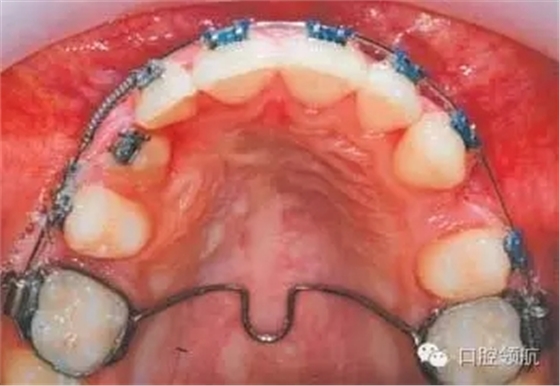

圖3.10中使用的矯治方法是什么?

在0.018英寸的不銹鋼圓絲上使用鎳鈦推簧為排齊UR3開拓間隙。在其作用下UR4遠(yuǎn)中移動,而UR2近中移動協(xié)助糾正中線不齊。使用彈性牽引力將UR3向遠(yuǎn)中、頰側(cè)移動,同時使用橫腭桿加強(qiáng)磨牙支抗。需要注意的是使用推簧開拓間隙時,應(yīng)保證UR2、UR4被動結(jié)扎于主弓絲上以防止扭轉(zhuǎn)。

為什么在此治療階段應(yīng)該選擇0.018英寸不銹鋼圓絲作為主弓絲?

首先,不銹鋼絲具有足夠的硬度,可以為彈性牽引提供支抗并防止其副反應(yīng)的發(fā)生(如牙弓變形等)。其次,圓絲可以降低滑動摩擦力,從而有利于牙齒移動。

該病例的下頜第二磨牙也被納入矯治,這樣做的優(yōu)點(diǎn)有哪些?

● 為減少覆深度提供垂直向支抗。

● 防止關(guān)閉間隙時第一磨牙的近中傾斜。

● 排齊第二磨牙。